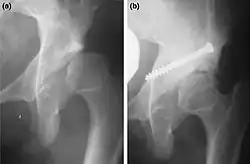

_open_reduction%252C_capsulorrhaphy_and_Dega_and_(b)_Chiari_surgery.jpg)

b. Same hip after addition of Chiari medial displacementosteotomy.[4]